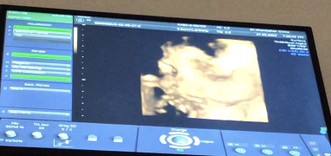

ขอดูตัวน้อยของแม่ไปทีมมกราคมหน่อยจ้า☺️☺️ อาการแม่ๆเป็นยังไงกันบ้างคะ บ้านนี้กินไม่ได้เลยกินนมก็ไม่ได้ออกทางเดิมตลอด🥺 #ทีมมกราคม 19 มกราคม 2566